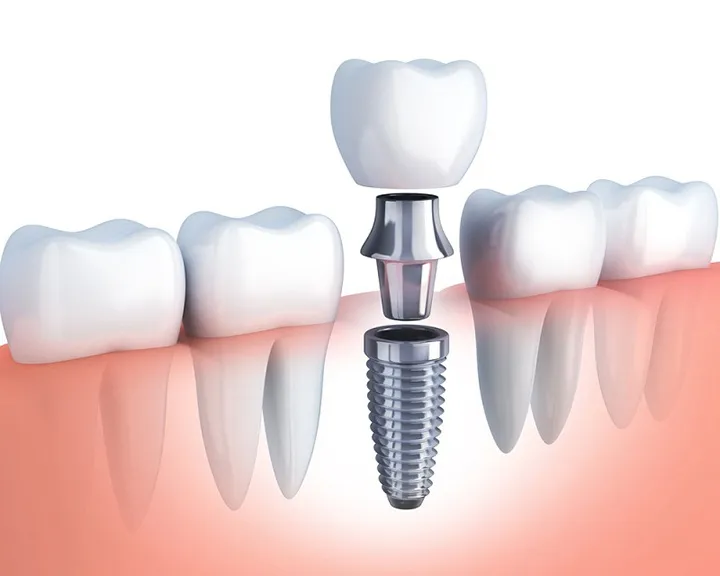

- Implant răng: Implant răng là một phương pháp phục hình hiện đại, sử dụng một trụ titanium cấy vào xương hàm để thay thế chân răng bị mất, sau đó gắn một mão răng giả lên trên. Implant răng có độ bền cao, không ảnh hưởng đến các răng lân cận và mang lại cảm giác ăn nhai tự nhiên như răng thật. Tuy nhiên, chi phí implant răng khá cao và thời gian điều trị kéo dài.

- Răng sứ: Mão răng sứ thường được sử dụng để làm mới một chiếc răng cối bị hư hỏng nhẹ. Tuy nhiên, trong trường hợp răng bị sâu lớn hoặc nứt vỡ, bác sĩ có thể kết hợp mão răng sứ với trụ implant để tái tạo lại răng cối hoàn chỉnh.